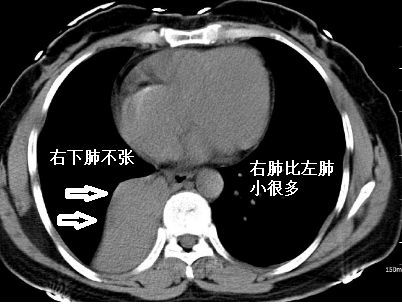

肺部ct右肺全肺不张

肺不张ct表现

肺不张ct表现图片

肺不张ct经典图片